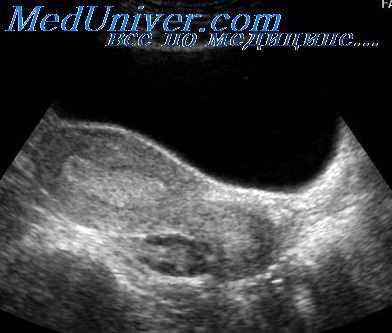

Киста селезенки:

• Ультразвуковые критерии: преимущественно анэхогенная структура очага;

- вариабельность размера; ровные, округлые края:

- часто периферическая кальцинация;

- иногда подвижные внутренние эхо-сигналы;

- ЦДЭ: отсутствие сосудов.

• Клинические банные: обычно протекает бессимптомно. Большинство первичных кист являются врожденными; вторичные кисты могут быть результатом предшествующей травмы, инфаркта, панкреатита или эхинококкоза.